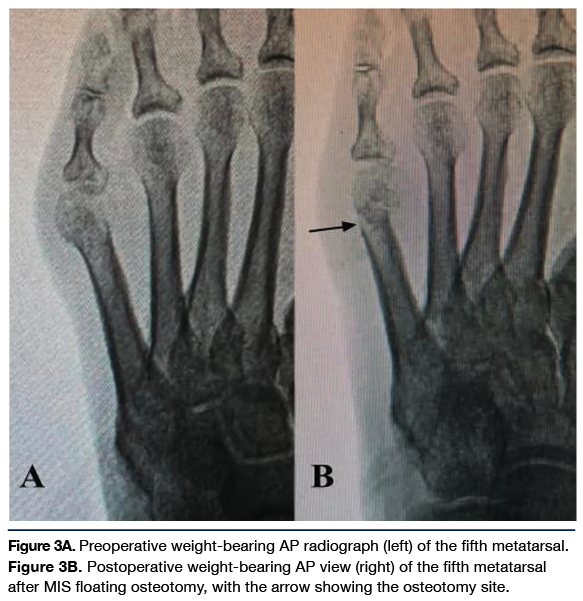

Case 1. A 64-year-old male with type 2 diabetes, peripheral neuropathy, and a recent amputation of the contralateral lesser digit due to osteomyelitis presented with a concurrent ulcer at the plantar fifth metatarsal head. After standard wound care and conservative offloading, that wound healed uneventfully. The patient ultimately had a recurrence of the wound with infection due to underlying bony deformity of the fifth metatarsal and excessive weight-bearing. After the infection was treated and osteomyelitis was ruled out, the patient agreed to surgical treatment for surgical offloading. A MIS floating fifth metatarsal osteotomy was performed to offload the chronic wound to achieve healing and prevent recurrence.

This patient was weight-bearing in a surgical shoe for 6 weeks and transitioned into supportive sneakers. There were no complications in skin or bone healing at 4 months and no recurrence of the wound. Tamir and team had 96% healing of their ulcers within an average of 3.5 weeks as well, and 38% of their MIS osteotomies involved the fifth metatarsal, with 27% involving the second metatarsal.7